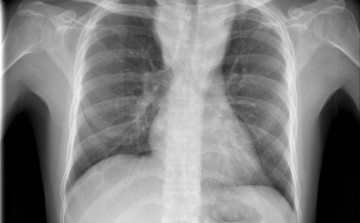

Csökkent a tbc-fertőzések száma Európában

Átlagosan 4,3 százalékkal csökkent az új tuberkulózisos (tbc-s) esetek száma 2010 és 2014 között az Egészségügyi Világszervezet (WHO) 53 országot magába foglaló európai régiójában.